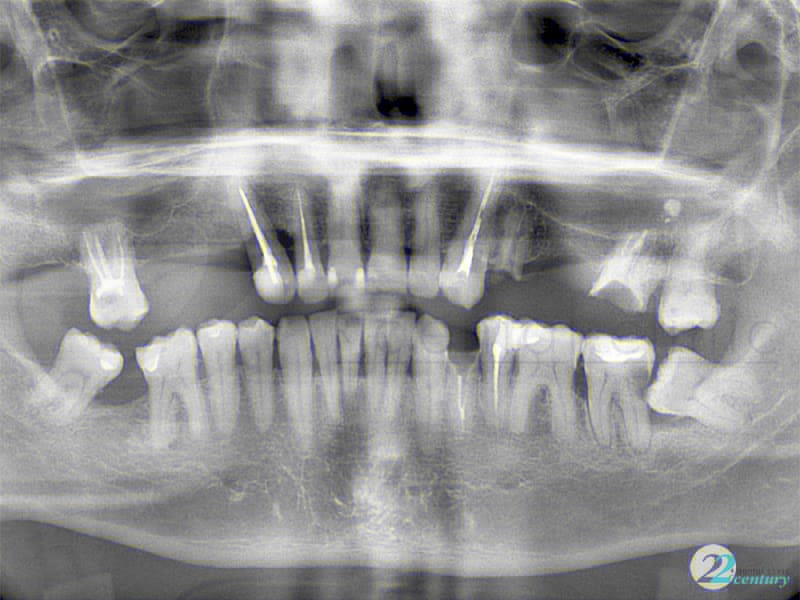

Примеры ортопантомограмм и их анатомия

Раздел: Фотоэссе